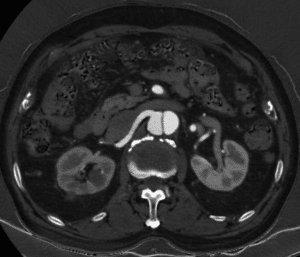

Imaging

Once you suspect a dissection, the next step is to show it. Imaging is done with ultrasound, computed tomography or MRI (and MR Angiography). Of these, the most useful are the CT and MR. But, the ultrasound can examine the flow in the artery. That is often very useful to understand if the function of the artery remained intact or not.